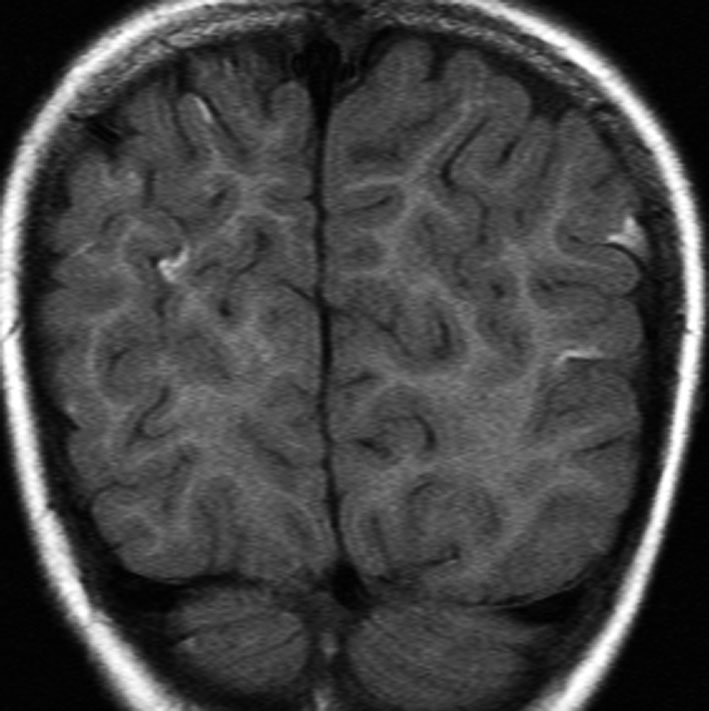

けいれん発作だけで発症した例

脳表のくも膜下腔がガドリニウム造影剤で白く造影されます。これはくも膜下腔ではなくて軟膜のメラノーシスが増強されているものです。髄液播種とは髄腔の見え方が少し違います。